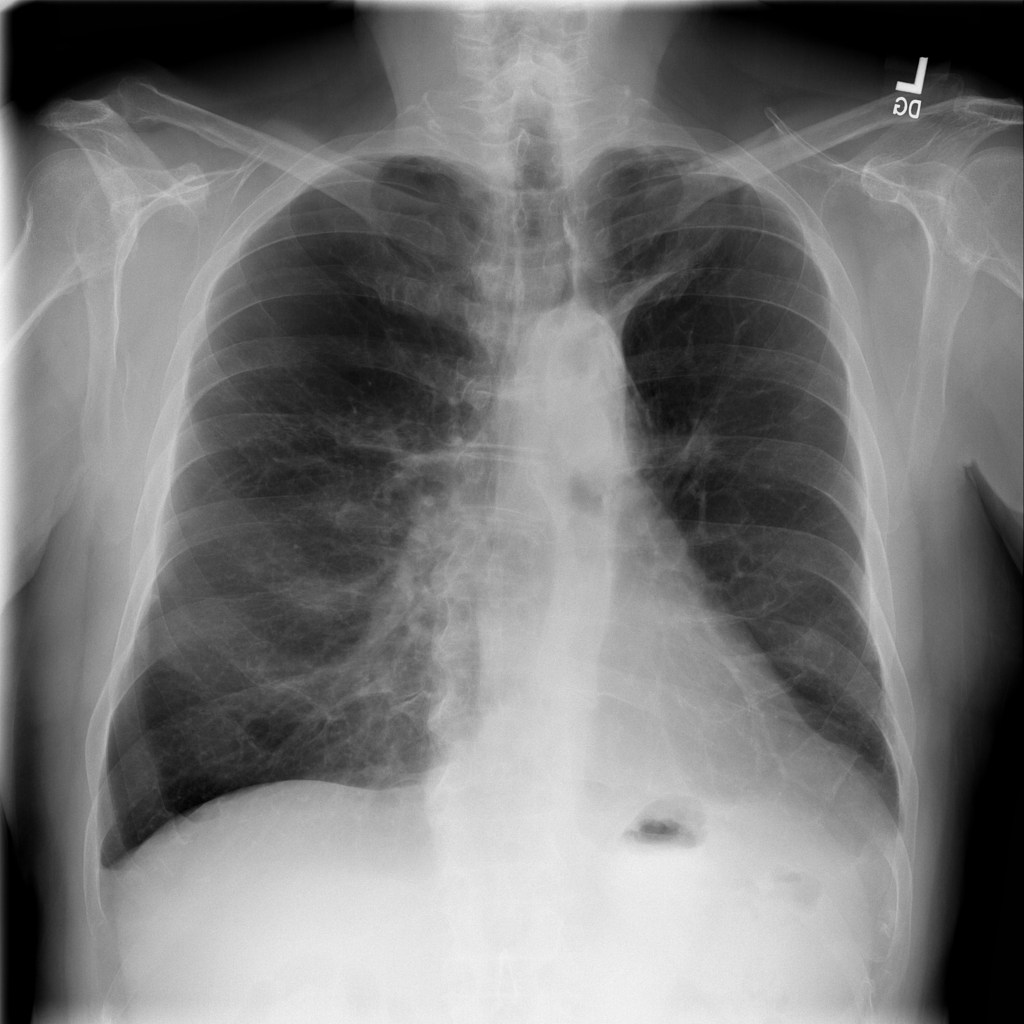

Showing up to 90 reference images for Hernia.

PAT-C048 · IMG-000Hernia

PAT-C048 · IMG-000

PA